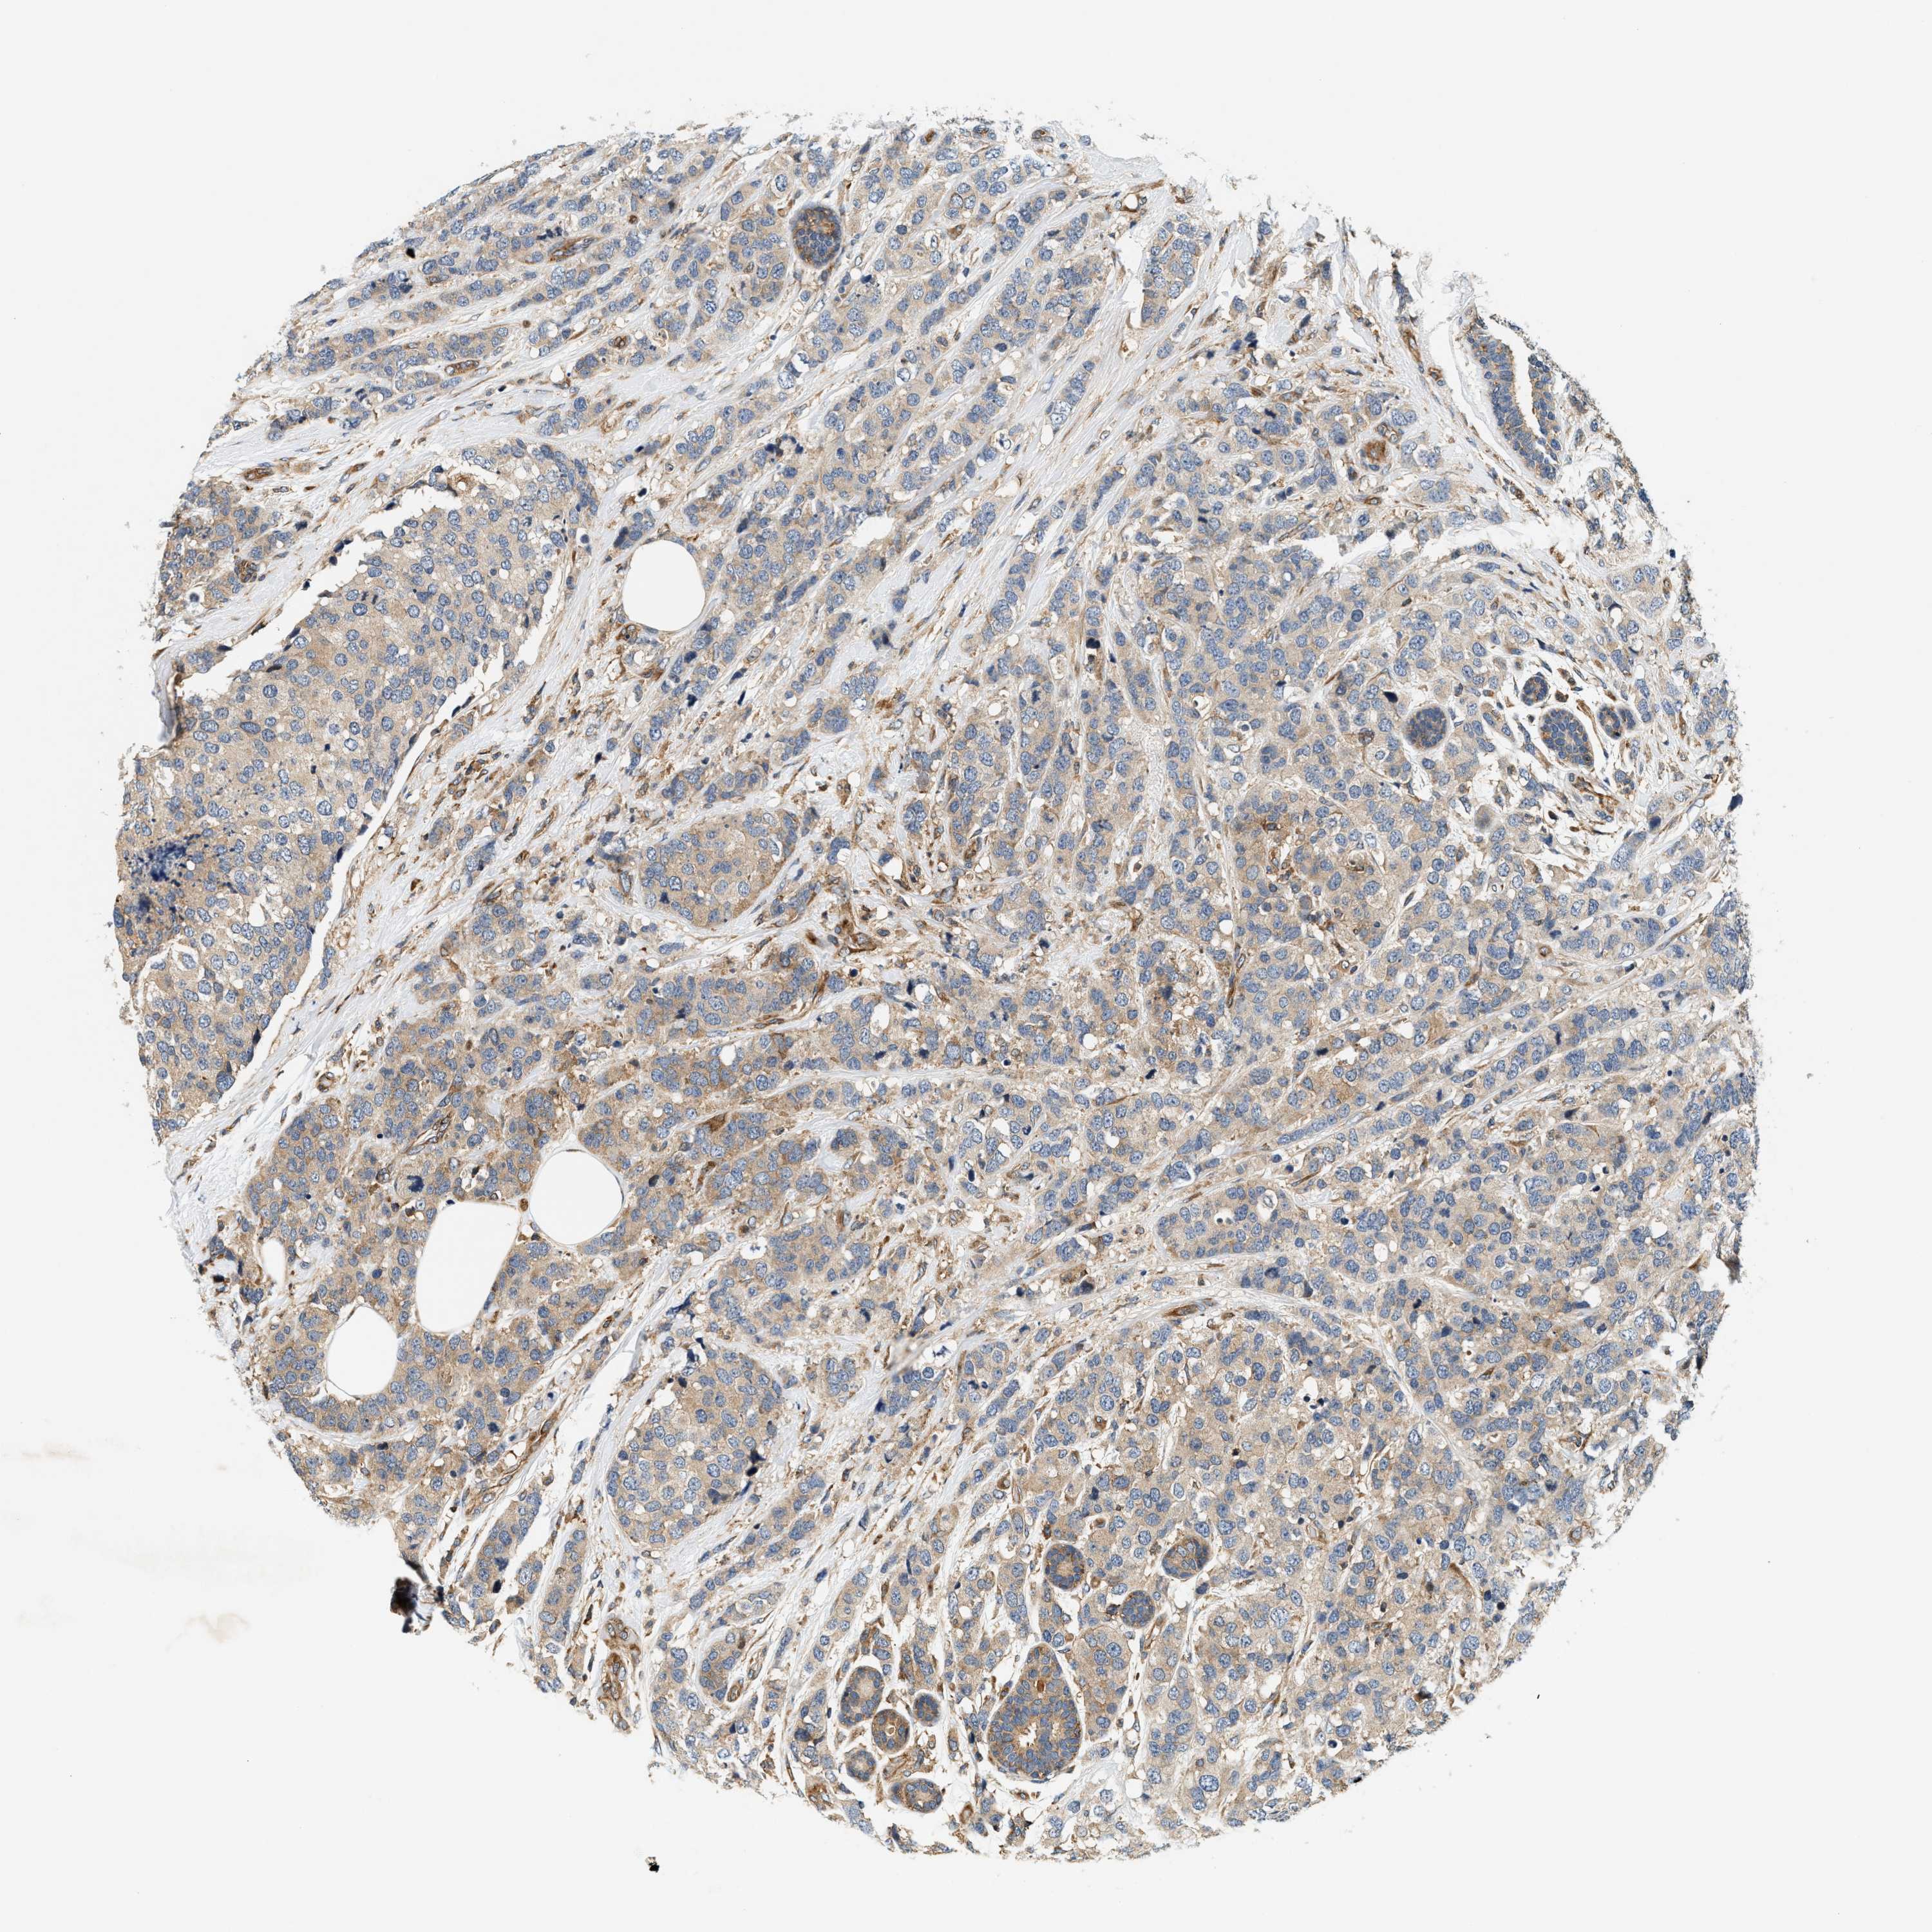

CANCER BREAST CANCER Show tissue menu

BRCA TCGA BRCA VALIDATION PROTEIN EXPRESSION

ANTIBODIES

AND

VALIDATION